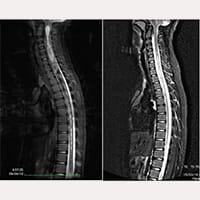

De 20 de outubro de 1993 a julho de 2017, foram realizadas intervenções de Secção do Filum terminale com a aplicação do FILUM-SYSTEM® em mais de mil pacientes que padecem da Síndrome Neuro-Crânio Vertebral e/ou da Doença do Filum, com Arnold Chiari I, Siringomielia e Escoliose (combinadas entre si de diversas formas).